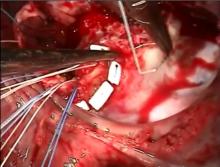

Excision of Obstructing Right Ventricular Mass and Tricuspid Valve Replacement [1]

This video shows the case of a young male who presented with a large obstructing ambiguous right ventricular mass that involved the tricuspid valve and the right atrium. The surgery consisted of an extirpation of this mass and replacement of the tricuspid valve. A brief case presentation is followed by the narrated operative video.